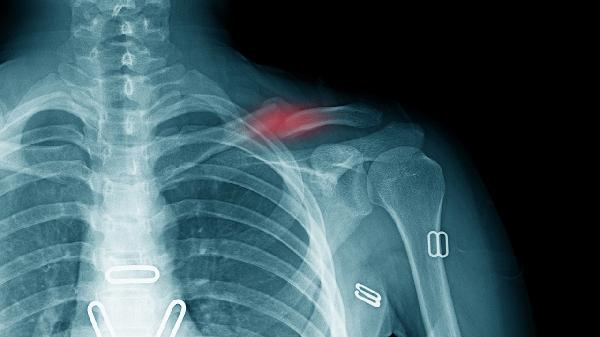

先天性胸廓畸形的严重程度因类型和个体差异而异,主要涉及漏斗胸、鸡胸、胸骨裂三类,需结合心肺功能评估、外观影响、并发症风险、治疗时机和长期预后综合判断。

漏斗胸可能导致心脏受压,严重时需3岁后手术矫正;鸡胸多影响外观,少数需胸骨矫形术;胸骨裂罕见但可能危及生命,需新生儿期紧急手术。Nuss手术、Ravitch手术和胸骨翻转术是常见术式。

重度畸形可能限制肺扩张,引发反复呼吸道感染或运动耐力下降。肺功能检查显示限制性通气障碍时,需考虑胸腔镜辅助微创手术。术后呼吸训练包括腹式呼吸、吹气球练习。